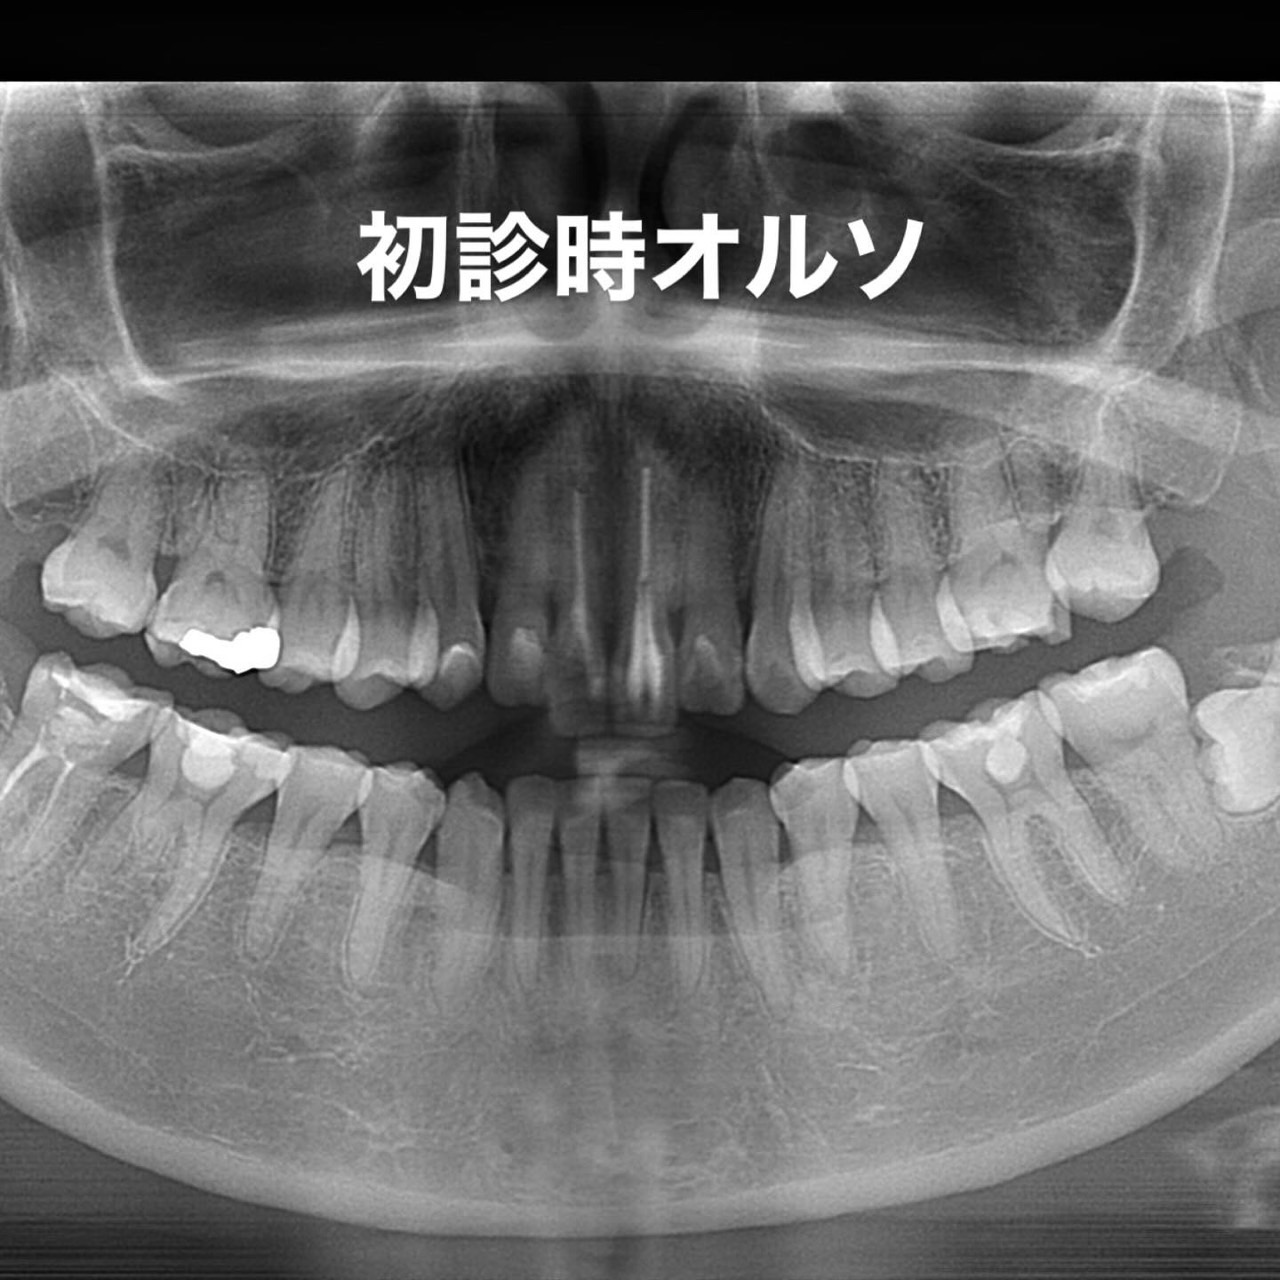

Case023

「歯の長さが短い、歯並びが歪んでる、表面が平面でカッコ悪い、歯茎が腫れている」ということを主訴に来院くださった患者様です。

歯茎の腫れは綺麗に歯を削り直して、正確に型を取り、

精密に作られたセラミックを適合よくセットしてあげることで、前医で入れてから1年以上腫れ続けてた歯茎が1週間で綺麗なピンク色に治りました。

形や並びに関しても、まず歯科医師が「どのような形にするか、どのように並べるか」をイメージしながら綺麗に削ることから始まります。

患者様の主訴通りに綺麗にできて喜んでいただきました。